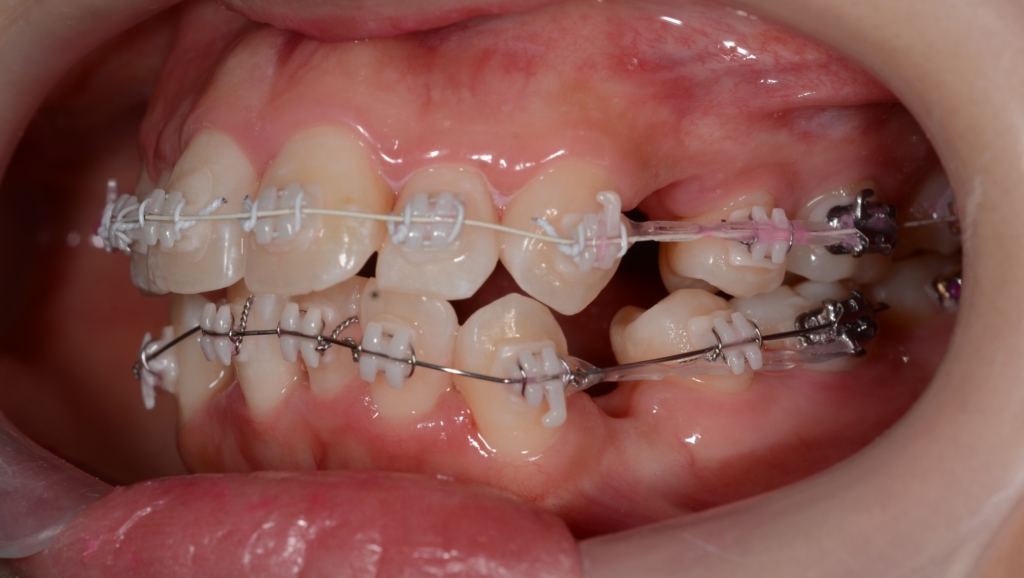

【5か月経過】

【隙間の閉鎖へ】

上下とも前歯はきれいに並びましたので、次のステップに移ります。

「口元がちょっとでも引っ込んで欲しい!」という」希望があったので、アンカースクリューを併用して治療を進めることにしました。

【アンカースクリューの植立】